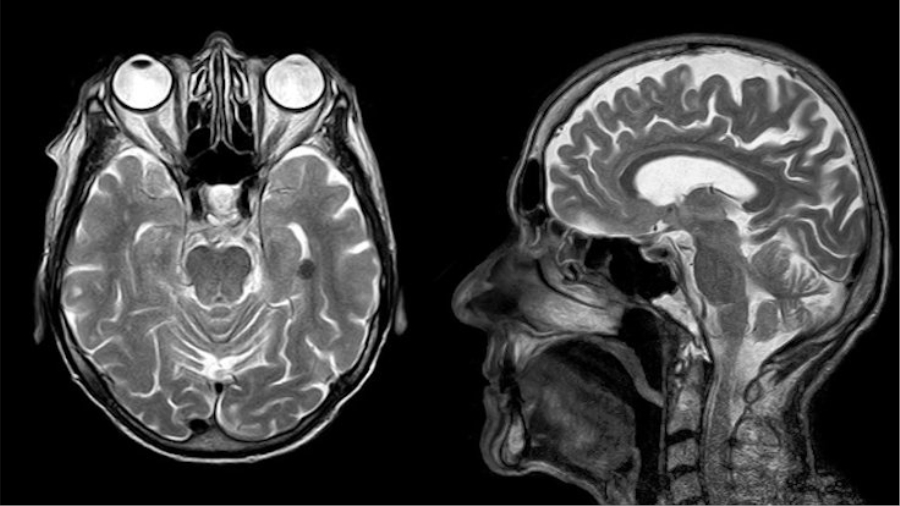

Yeni tür korona virüsünün kalıcı ve ölümcül beyin hasarına yol açtığı tespit edildi. İngiltere’de yapılan bir araştırma, Covid-19’un özellikle semptomları hafif geçiren kişilerde nörolojik sorunları tetiklediğini ortaya çıkardı. UCL Noröloji Enstitüsü’de 40’tan fazla hasta üzerinde yürütülen çalışmada virüsün merkezi sinir sistemi iltihabı, deliryum (bilinç bulanıklığı) ve felcin yanı sıra akut dissemine ensefalomiyelit (ADEM) hastalığını da tetiklediği kaydedildi.

Çalışmada, korona vakalarıyle eş zamanlı olarak merkezi sinir sistemini etkileyen akut dissemine ensefalomiyelit (ADEM) vakalarında artış olduğu tespit edildi. UCL Noröloji Enstitüsü’nde, ayda bir görülen ADEM vakalarının nisan ve mayıs aylarında haftada üçe çıktığı belirtildi. 59 yaşında bir kadının da ADEM nedeniyle öldüğü aktarıldı.

Yaklaşık 12 hastada merkezi sinir sistemi iltihabı, 10 hastada deliryum, sekizinde felç ve başka sekiz hastada felce neden olan Guillain-Barré sendromu tespit edildi. Zandi, “Covid-19’un, daha önce başka virüslerde tespit etmediğimiz, beyin hasarlarına neden olduğunu görüyoruz” dedi. Artan ADEM vakalarıyla ilgili olarak ‘bazı hastaların iyileştiği ancak bazılarında uzun süreli sakatlığa neden olduğunu’ aktardı.